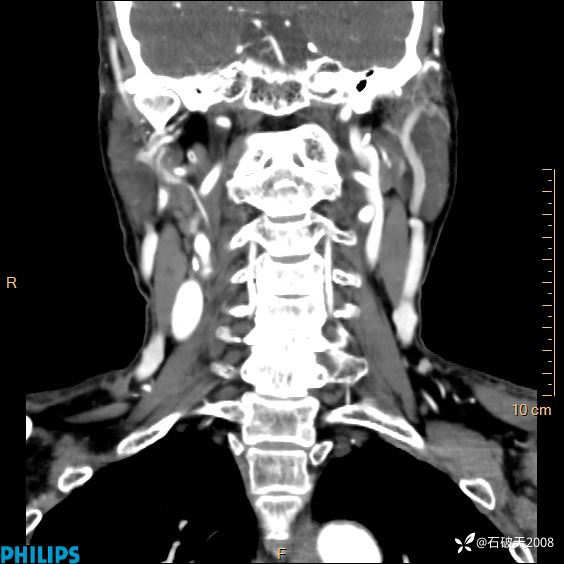

冠状位